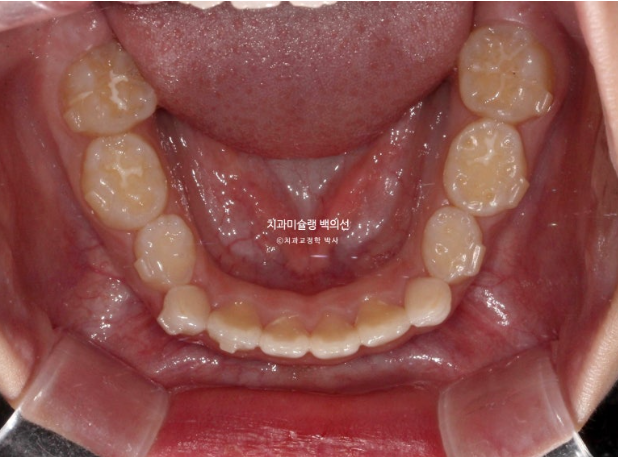

2022년 8월 내원한 어린이 입니다.

앞니 반대교합과 비대칭 치료를 위해 오셨습니다.

앞니 뿐 아니라 송곳니, 일부 어금니까지 거꾸로 물리는 상황입니다.

앞니 반대교합은 프리올소와 같은 장치로 간단하게 넘겨줄 수 있지만 더 큰 문제는 비대칭입니다.

아래앞니와 함께 아래턱이 우측으로 돌아가 있습니다.